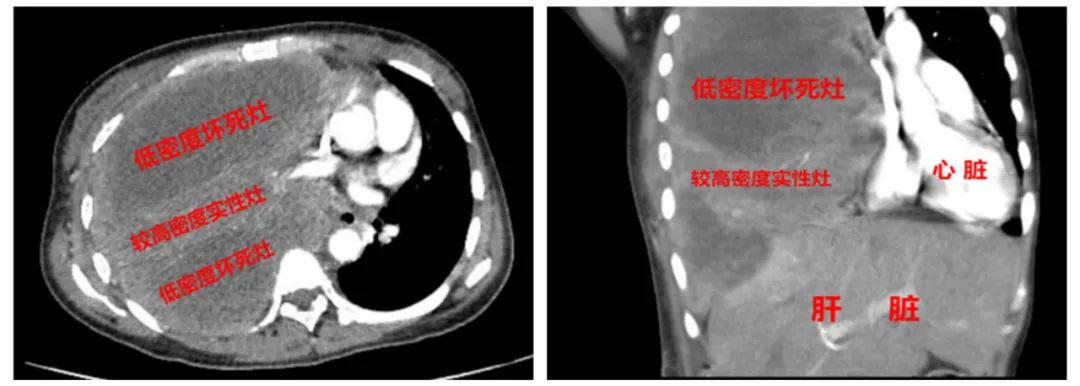

患者来我院前在外院确诊为:右肺肉瘤样癌伴胸膜、纵隔淋巴结转移( cT1cN2M1a,IVa期),予白蛋白紫杉醇+卡铂+替雷利珠单抗等药物化疗,经治疗后患者出现骨髓抑制,遂来我院就诊。经复查胸部增强CT扫描提示右肺占位性病变较前增大、右侧胸膜多发转移瘤较前增大、纵隔淋巴结肿大。罗少华主任带领呼吸与危重症医学科进行科内病例讨论。考虑:患者当前治疗效果不理想,肺肉瘤样癌是预后极差的一类罕见肺癌,急需寻找更有效的治疗方案,且因患者外院所取标本质量欠佳,肿瘤细胞数量较少,未能满足基因检测要求,建议患者再次行经皮肺穿刺活检术;再次活检的关键点,是要穿刺密度较高实性病灶,避开大片的低密度坏死灶,可借助超声引导施行肺穿刺活检术。

胸部CT示:巨大肿物占据整个右肺,大片低密度坏死灶。